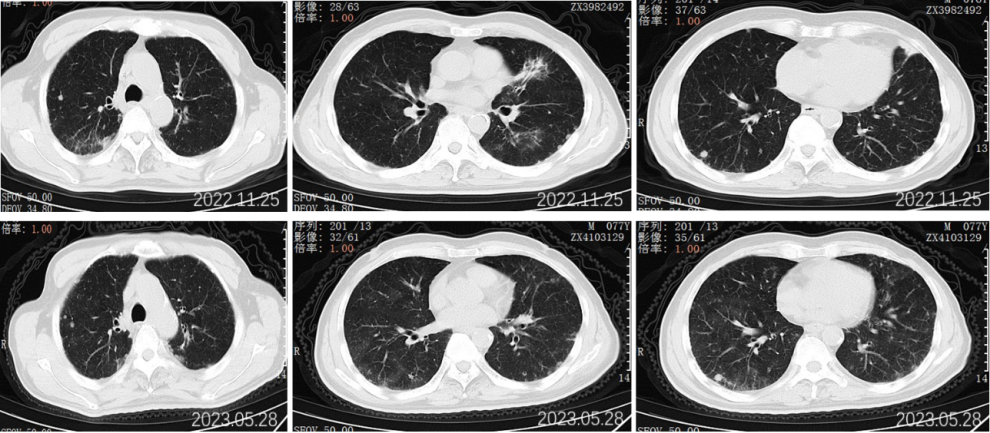

2022.09.27胸部CT平扫:1.两肺多发小结节、类结节影,较前相似,转移性考虑;2.两侧胸腔少量积液较前已吸收。3.左侧第5后肋骨质破坏。

2022.11.25胸部CT平扫:对比2022-09-27影像:1.新见两肺多发间质性肺炎样改变,感染考虑,VP-RADS 2类;2.两肺多发小结节、类结节影,部分较前略缩小,转移性考虑;3.左侧第5后肋骨质破坏,相仿。

2023.5.28胸部CT平扫:对比2022-11-25片:1.两肺散在多发炎症,较前相仿,VP-RADS 2类;2.两肺多发小结节、类结节影,转移瘤考虑,较前相仿;3.左侧第5后肋骨质异常,相仿。男性乳腺发育。

2023.09.29胸部CT平扫:对比2023-05-28片:1.两肺多发小结节、类结节影,较前增多增大,转移瘤考虑。2.两肺散在多发炎症,部分较前吸收;3.左侧第5后肋骨质异常,相仿;4.右侧胸腔少量积液。男性乳腺发育。